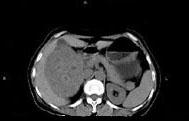

问题 女,57岁,右腰部胀痛6个月余,触及右侧腹部包块2个月,CT平扫及增强如图所示,下列说法正确的是 ( )

选项 A、考虑肿块来源于右肾,是巨大的肾癌,并挤压推移右肝,与其分界欠清 B、考虑肿块来源于右肾,是肾血管平滑肌脂肪瘤,并挤压推移右肝,与其分界欠清 C、增强扫描肿块强化明显,其内可见无强化的低密度坏死灶 D、考虑肿块来源于肝脏,是原发性肝癌,并挤压推移右肾 E、平扫时可见右侧腹部巨大的软组织肿块影,其内可见小片状的低密度影

答案 ACE